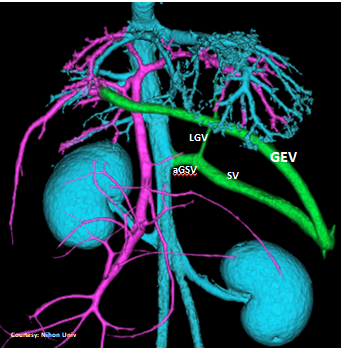

“LGC +RGV +SGV”

Left Gastro-Caval Shunt with Right Gastric Vein and Short Gastric Vein contributions

Courtesy: Nihon Univ